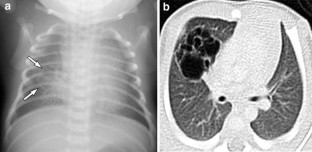

Fig. 3